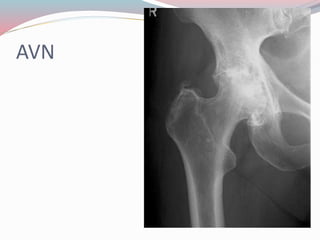

๏‚— AVN

AVN

COMPLICATION OF FRACTURE ๏‚—Delayed union ๏‚— Nonunion ๏‚— Malunion ๏‚— AVN ๏‚— Traumatic subperiosteal ossification ๏‚— Myositis osificans ๏‚— Sudeckโ€™s osteodystrophy